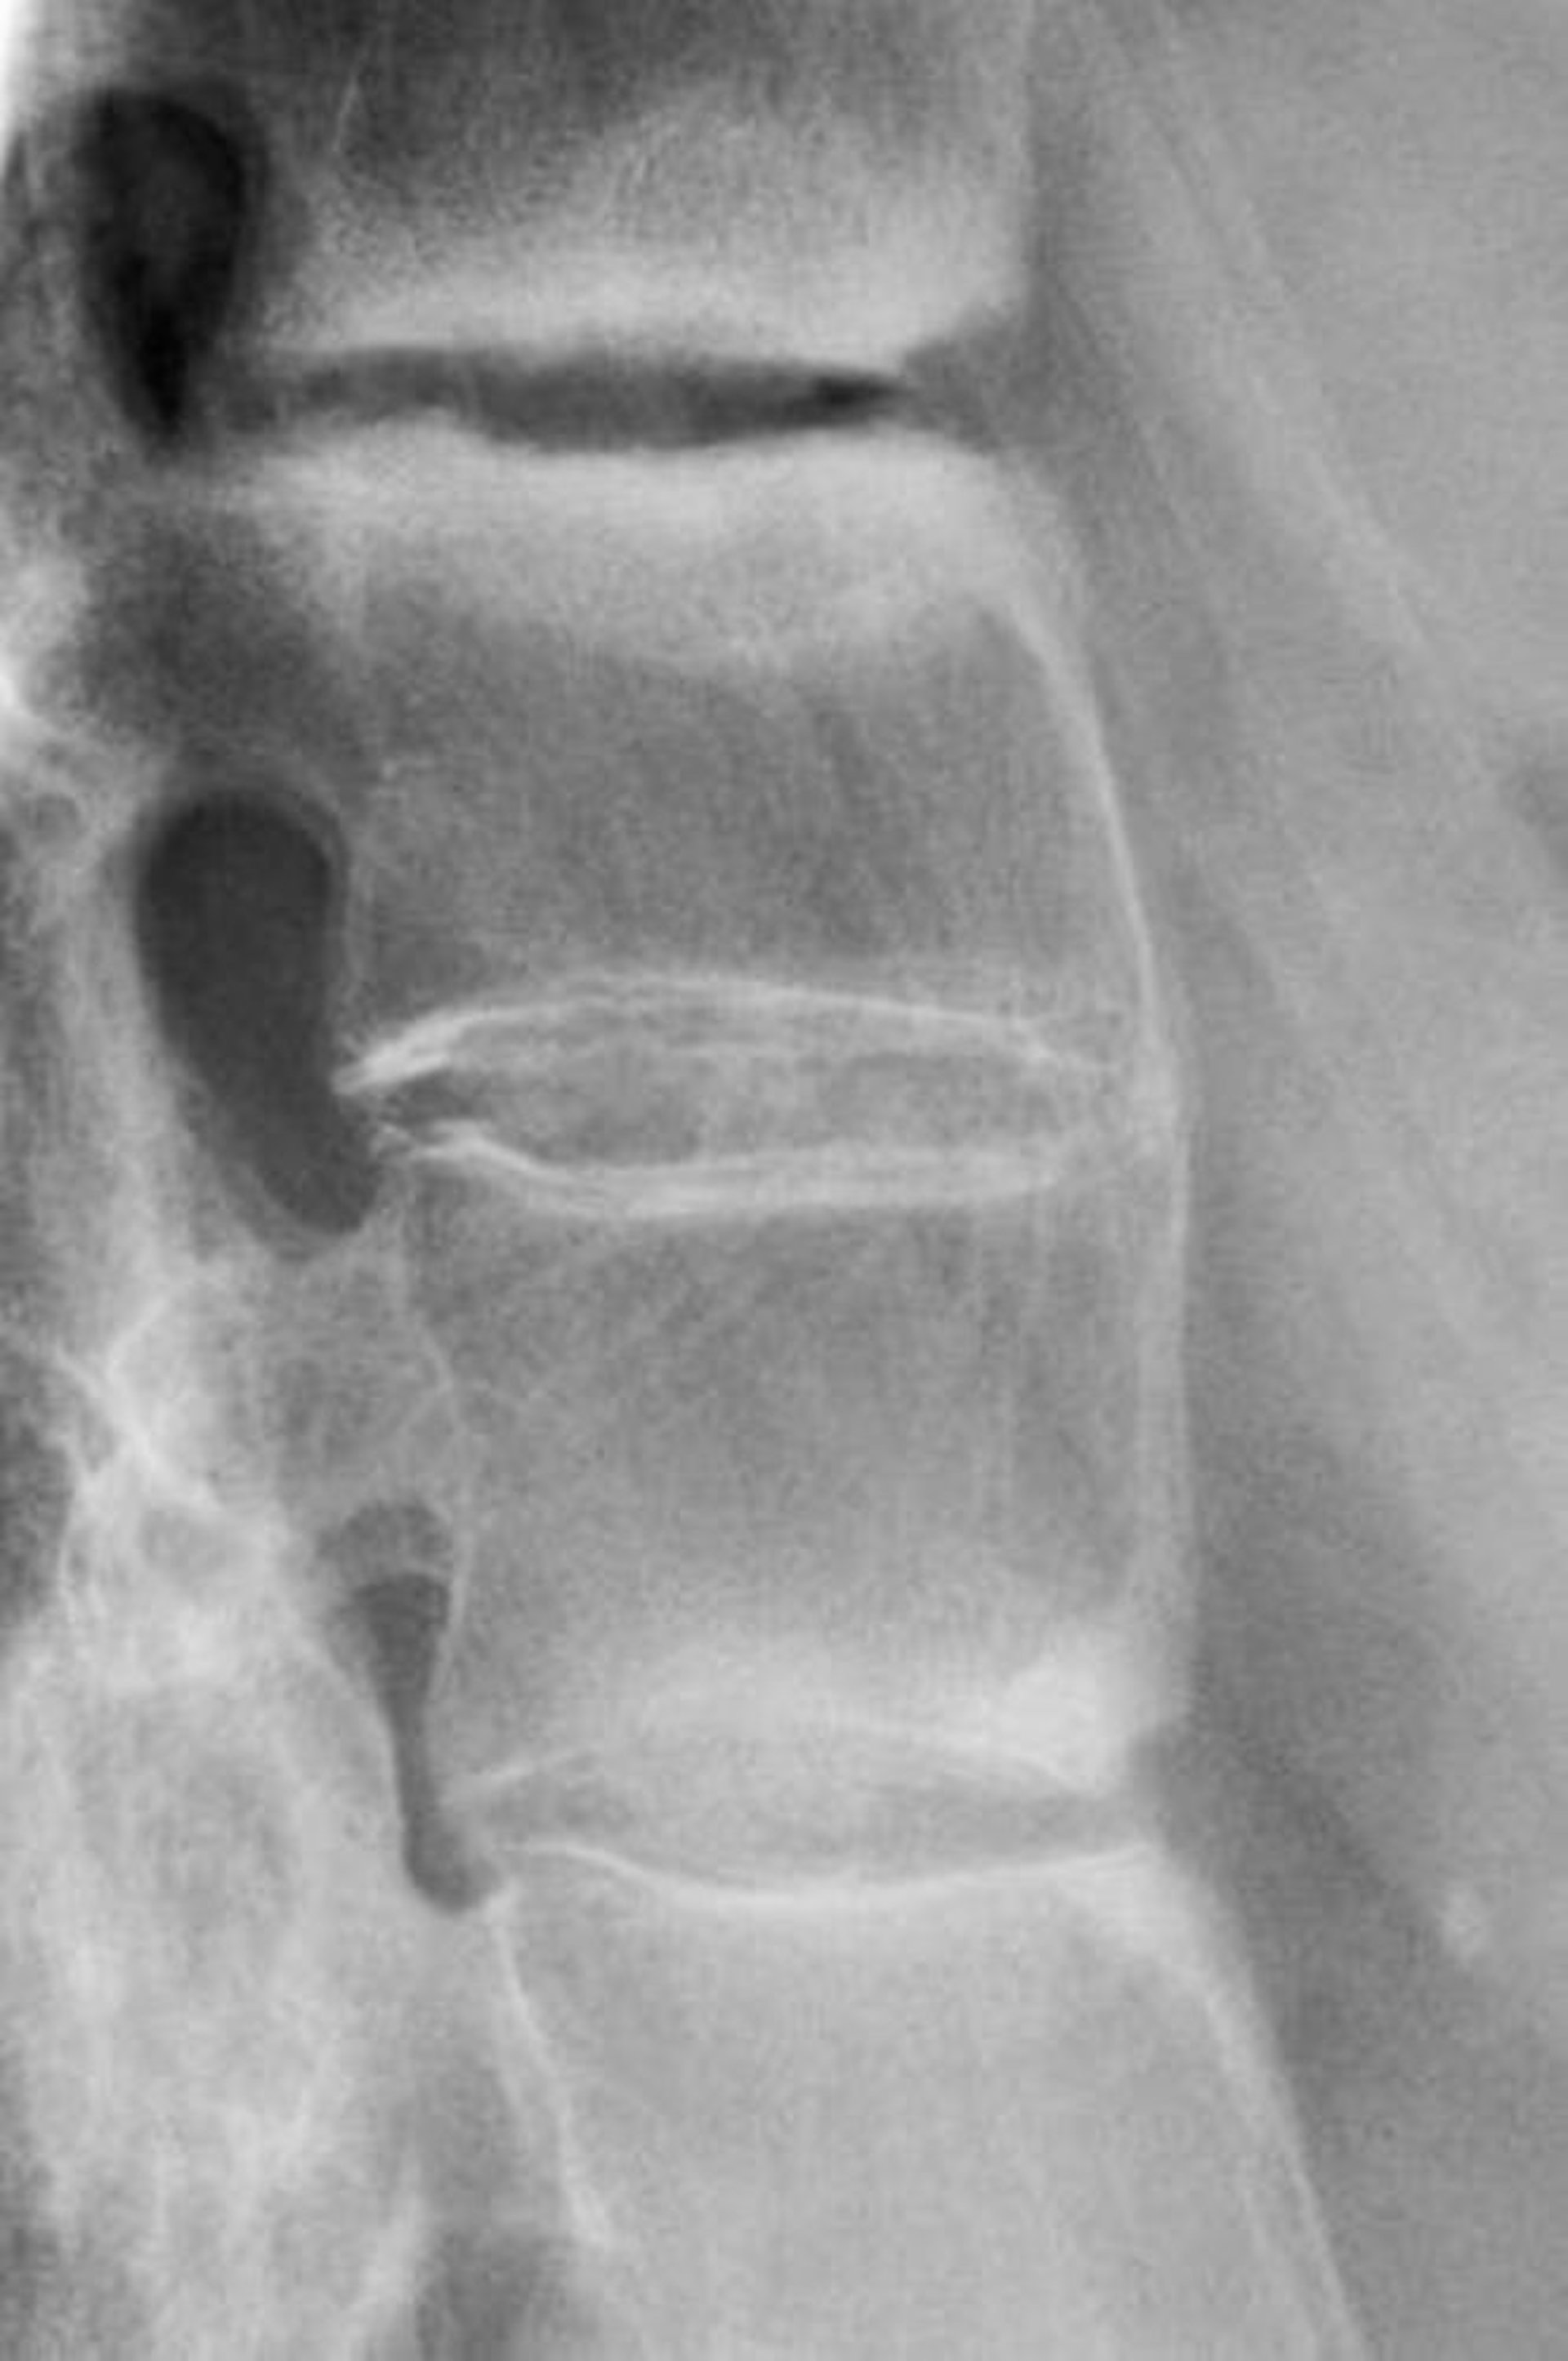

Espondilitis anquilosante

Esta radiografía muestra esclerosis entre las vértebras lumbares, pérdida de la lordosis y fusión de las vértebras lumbares, un hallazgo que indica espondilitis anquilosante avanzada.

DR P. MARAZZI/SCIENCE PHOTO LIBRARY